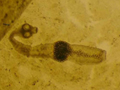

Der geschlechtsreife, nur wenige Millimeter lange Bandwurm lebt im Dünndarm seines Endwirtes. Wie alle Bandwürmer braucht er einen Zwischenwirt, in dem sich die Entwicklung zur Bandwurmfinne vollzieht.

Der Entwicklungszyklus des Fuchsbandwurms spielt sich hauptsächlich in einem Kreislauf unter Wildtieren ab. Der Fuchs als Endwirt beherbergt den geschlechtsreifen Wurm und scheidet mit seinem Kot Bandwurmeier aus. Mäuse und Bisamratten nehmen die Eier mit ihrer Pflanzennahrung auf und werden dadurch zu infizierten Zwischenwirten. In den inneren Organen dieser Zwischenwirte vollzieht sich die Entwicklung zur Bandwurmfinne. Die Kleinnager wiederum werden vom Fuchs als Hauptbeutetiere gefressen. So gelangt die Bandwurmfinne in den Endwirt, in dessen Darm sie sich zum geschlechtsreifen Bandwurm entwickelt.